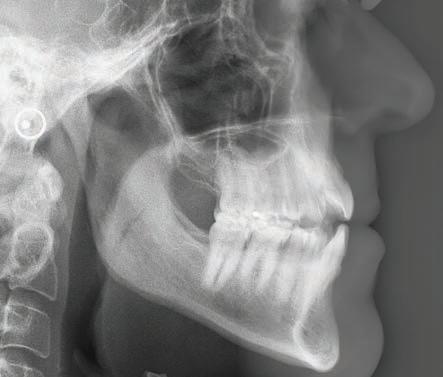

The panoramic radiograph (Figure 3) highlights the three missing premolars and absence of all third molars. Root length is excellent and periodontal support is good. The patient’s restorative index is low, a reflection of his history of regular dental care and good oral hygiene. The cephalometric radiograph, and analysis (Figure 4a and 4b) suggest a near-Class I skeletal relationship with mildly increased skeletal vertical dimension (MPA 35.8). Mandibular incisor angulation is significantly below average (IMPA 84.7), relative to the steeper than average mandibular plane. Visually, incisor angulation appears to be normal.

Figure 3: INITIAL panoramic radiograph Figures 4a and 4b: Initial cephalometric radiograph and analysis